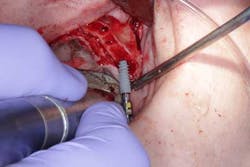

Surgery commenced. Implants on the lower arch were placed first (figures 7 and 8) and then we switched to the maxillary. The teeth were removed (figures 9 and 10) and the ridge was evened out (figures 11-13). The implants were aligned with the denture (figure 14) and then placed accordingly (figures 15-17). Healing caps were put on, and we were ready to start the restorative phase (figures 18-19).